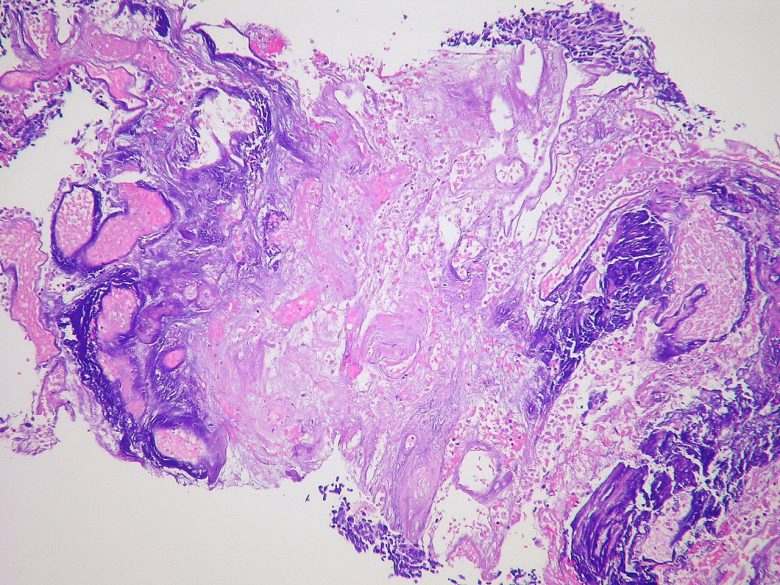

Image Credit: Cancer Research UK / WIkimedia Commons.

Brain cancer

“Brain and spinal cord (also known as central nervous system, or CNS) tumors can be benign or malignant.”